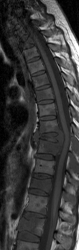

Вот МРТ картина:

Аномалия развития тел грудных позвонков Th2, Th9(бабочковидные позвонки, частичная конресценция дужек), Th12 клиновидная форма. Сдавление межпозвоночного канала.

Коллеги, а какой аномалии может идти речь??? На МРТ все признаки поражения костного мозга тел и ножек позвонков, инфильтрация с снижением сигнала на Т1, эти изменения видны на нескольких уровнях. Ищите онкологию (лимфому например) или патологию крови. А натечника никакого нет; сдавление спинного мозга значительное.

Коллеги, по рентгенограммам: полностью разрушен Th9, литическая деструкция правой половины тела и дужки Th10, литическая деструкция с патологическим компрессионным переломом Th12... Какая "бабочка"?!